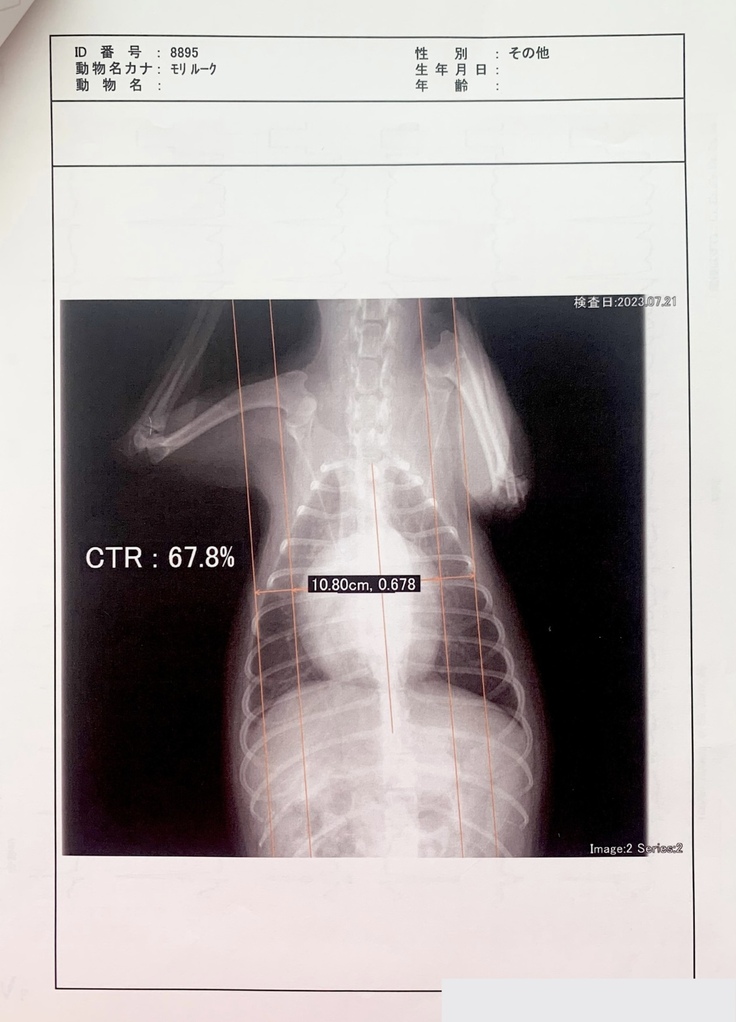

その後、また呼吸が苦しそうで一度酸素室に2日ほど入院しました。そして、僧帽弁閉鎖不全症手術の名医がいる病院を紹介され、そこで検査を受けてきた次第(7/21)です。

重症と診断され、手術は8月中に受けられる見込みとなりました。

手術を行う病院での検査(7/21)以降、自宅で安静にしていますが、心臓が肥大していることから出る咳が頻発すること、僧帽弁閉鎖不全症後期である泡のような嘔吐の症状があるため、通院/検査をしながら日々を送っております。